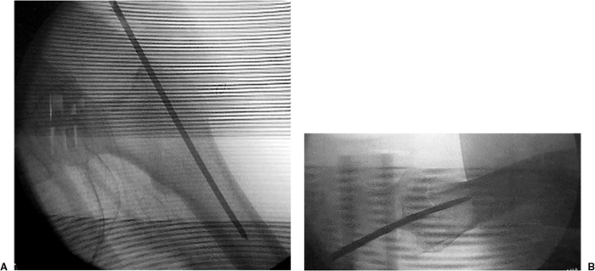

should be verified with bi-planar imaging. Using a freehand technique,

we insert a 3.2-mm guide pin percutaneously (Fig. 17.6),

about 3 to 4 cm proximal to the trochanter, engaging the bone at or

just medial to the tip of the greater trochanter. This location will

counteract the tendency toward varus and increased neck-shaft offset as

well as minimize any damage to the gluteus medius insertion (Fig. 17.7). Based on the lateral view, the guide pin should be centered in the canal (Fig. 17.8A), and based on the AP, it should be aimed slightly medial (Fig. 17.8B).